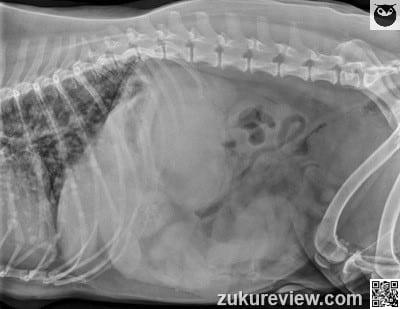

Which one of the following choices is evident on these radiographs from a ten-year-old cocker spaniel with anemia?

This dog has metastatic disease. There are multiple small soft tissue nodules throughout the lung fields and two masses in the abdomen.

One abdominal mass is visible between the left kidney and the fundus of the stomach (lateral and v/d views). The second mass is in the caudoventral abdomen, visible only on the lateral projection.

Click this link to see the dorsal mass in the dorsal extremity (head) of the spleen, and the distal mass in the ventral extremity (tail) of the spleen. The more dorsal tumor is causing a mass effect, displacing the left kidney caudally compared to the right kidney (visible on v/d).

This dog had metastatic hemangiosarcoma (HSA). The spleen, right auricle, skin, and subcutaneous tissues are the most common sites, but HSA can arise anywhere.